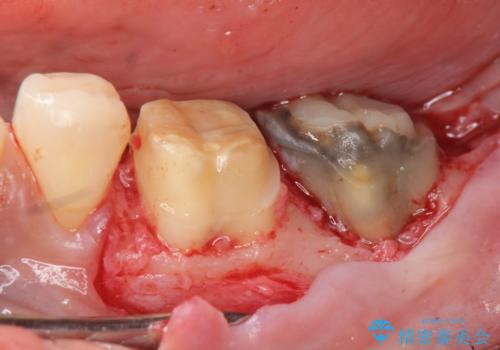

このままの状態でクラウンのやりかえを行うと高さが低く安定の悪いクラウンとなってしまうため、事前に歯周外科手術を行い歯ぐきを下げることで安定性の高いクラウンを製作する治療計画としました。

高さの低いクラウンはセメントが漏出しやすく脱離しやすいだけでなく虫歯の再発の可能性も高まってしまいます。